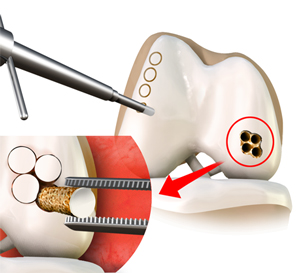

Mosaicplasty

What is Mosaicplasty? Weight-bearing joints, such as the knee, may develop defects in the articular cartilage (spongy tissue that lines and cushions …